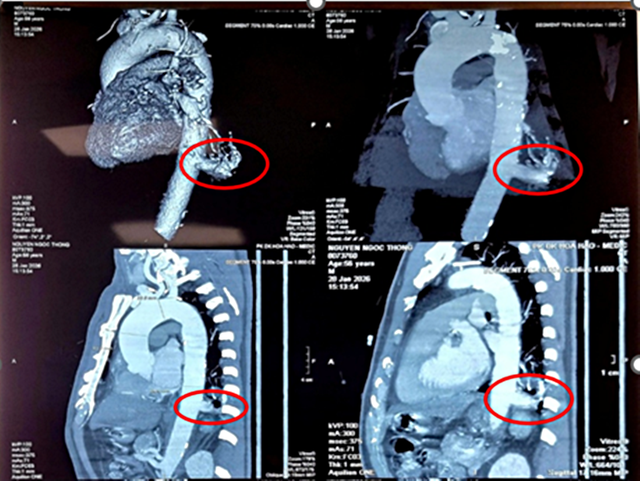

Người bệnh là ông N.N.T (56 tuổi, Tây Ninh), tình cờ phát hiện tổn thương ở thùy dưới phổi trái khi khám sức khỏe tổng quát. Kết quả chụp cắt lớp vi tính cho thấy khối phổi biệt lập kích thước 23x26mm.

Điểm đáng lo ngại là động mạch nuôi khối này xuất phát trực tiếp từ động mạch chủ ngực xuống, đường kính lên tới 17mm – kích thước lớn, tiềm ẩn nguy cơ chảy máu ồ ạt nếu vỡ.

Hình chụp MSCT lồng ngực ông T. Ảnh: BVCC.